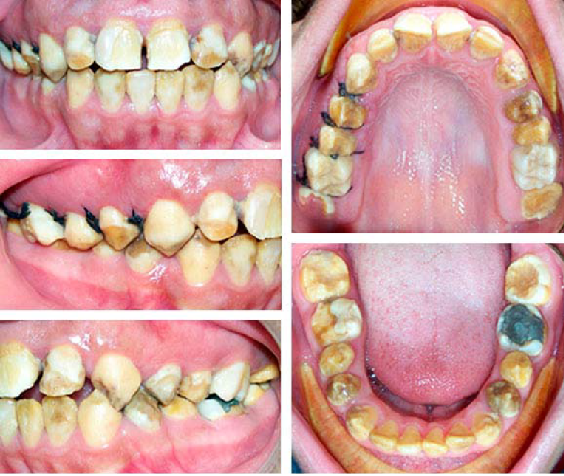

Paciente femenino de 35 años de edad, que corresponde a la madre y que al examen clínico presenta zonas de dentina expuesta en los tercios incisales de los dientes anteriores inferiores asociadas a hipomaduración del esmalte y fragmentación por desgaste en los bordes incisales. En los dientes posteriores se observa exposición de la dentina asociada a hipomaduración y fragmentación del esmalte en la zona oclusal. En los dientes anteriores, el esmalte se observa blanco y con pérdida de brillo por hipomaduración; mientras que en los posteriores se observa amarillo, con pérdida de brillo y de aspecto rugoso por descalcificación. Se presumen que las fragmentaciones ocurren a nivel de la unión amelodentinaria (falla adhesiva), bien porque el esmalte no se formó; o si lo hizo, no desarrolló un patrón de unión festoneado adecuado, por lo que posteriormente se fragmentó durante la función masticatoria exponiendo la dentina al desgaste. Diagnóstico presuntivo: amelogénesis imperfecta del tipo hipomadura Tipo II (Fig. 1).

Paciente masculino de 13 años de edad, que corresponde al hijo mayor y que al examen clínico presenta el esmalte de todos los dientes superiores e inferiores permanentes afectados de alguna forma. Existe ausencia de desarrollo del esmalte con amplias zonas de dentina expuesta, esta última opaca y con manchas pardas generalizadas. En algunos casos en donde el esmalte persiste se observa blanco y brillante, mientras que otras veces se observa opaco, rugoso y discontinuo por descalcificación. Se presumen que la ausencia, fragmentación y perforaciones del esmalte ocurren a nivel de la unión amelodentinaria (falla adhesiva), sin involucrar a la dentina. Es posible identificar lesiones de esmalte hipomaduro e hipomineralizado. Se pueden observar diastemas dentales asociados a fragmentación del esmalte interproximal por disminución de su resistencia en la distribución de las fuerzas transversales durante la función de masticación y disminución del volumen de la corona por excesivo desgaste. Diagnóstico presuntivo: amelogénesis imperfecta del tipo hipoplásica Tipo I (Fig. 2).

Paciente masculino de 9 años de edad, que corresponde al hijo menor y que al examen clínico presenta el esmalte de todos los dientes permanentes afectados de alguna forma, asociados a lesiones de hipocalcificación. Predominan las lesiones en forma de copo de nieve o motas de algodón, sobre todo en las superficies vestibulares, con perforaciones asociadas a hipoplasias puntuales que traslucen la dentina subyacente de color amarillo pardo. Diagnóstico presuntivo: amelogénesis imperfecta del tipo hipomadura Tipo II (Fig. 3).

Durante la odontogénesis, la unión amelodentinaria (UAD) se comporta como la plataforma de inicio de la amelogénesis y de la dentinogénesis configurando una interfase festoneada entre el esmalte y la dentina, mucho más imbricada en la región de las cúspides.18,19 Esta UAD disipa las fuerzas generadas durante la masticación, optimizando el comportamiento microestructural de ambos tejidos.20 Por tanto, si hay una alteración genética en la síntesis de los componentes de la matriz extracelular desde el inicio de la amelogénesis, la UAD no quedará conformada de forma adecuada, lo que afecta el patrón festoneado y ocasiona que ante la función masticatoria se venza el escaso límite de resistencia y se fragmente el esmalte en la unión con la dentina. Esto asociado a que la microdureza del esmalte se ve afectada, mucho más en el fenotipo hipocalcificado que en el hipomaduro,21 tal como se puede observar en las figuras 1 y 2.

Dicha fragmentación resulta evidente en las superficies vestibulares y linguales donde la UAD morfológicamente es menos festoneada en los bordes incisales y vértices cuspídeos por la atrición y en la región cervical ante el cambio dirección y menor longitud de los prismas de esmalte por abfracción. En contraste, en los pacientes con fenotipo hipomaduro que mantienen el esmalte afectado poroso y adherido a la dentina, como se observa en la figura 3, la alteración de los prismas ocurre en la superficie, por lo que se considera que la AI ocurrió en la fase de maduración, razón por la cual los defectos estructurales ocasionados por la constitución de un esmalte aprismático se asocian con la disminución de actividad de los ameloblastos y el deterioro del proceso de Tomes durante el ensamblaje final del prisma.21